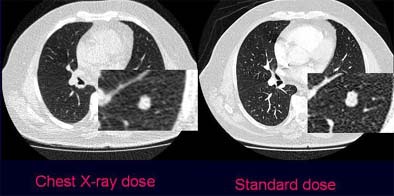

![]() |

| Axial images show pulmonary nodule in standard dose (right) and ultra-low-dose scan protocols in a 64-year-old patient with prostate cancer. The zoomed images show one of two metastases that were histologically confirmed and resected. All images courtesy of Dr. Valentina Romano. |